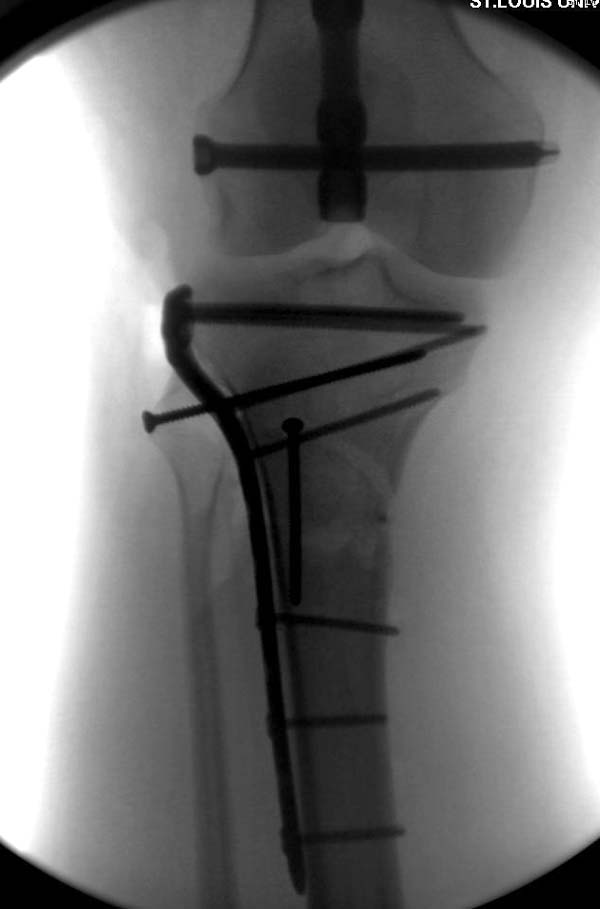

Здесь, кроме перелома верхней трети голени, имеется вовлечение сустава, и, чтобы не пропустить смещение суставной поверхности, надо делать КТ. Срезы КТ покажут о необходимости субхондральной фиксации, которая проводится 3.5 мм параллельными шурупами (Raft technique). Не имеет значения, как проводить: отдельно субхондрально или через верхний ряд пластины. Главная задача фиксации удержать суставную поверхность от коллапса в вальгус или варус.

Фактически все компании выпускают проксимальные с угловой стабильностью пластины. Можно от DePuy, потому что у них имеются различные варианты преконтурированных пластин, подходящих для любой голени. http://www.biomet.com/traumaTransition/fileLibrary/BMET0001.0ALPSProxTibia.pdf

Кроме этого, у них имеются более толстые полиаксиальные, но в данном случае это не имеет значения, потому ято в любом варианте нагрузку можно разрешить только после 10-12 недели. http://www.biomet.com/traumaTransition/products/platesScrews/polyaxPeriarticularPlatingSystem.cfm#overview

Здесь случай, так называемого floating knee перелома выше и ниже коленного сустава.

Имя     : 6 Proximal tibia injury pelvis.JPG